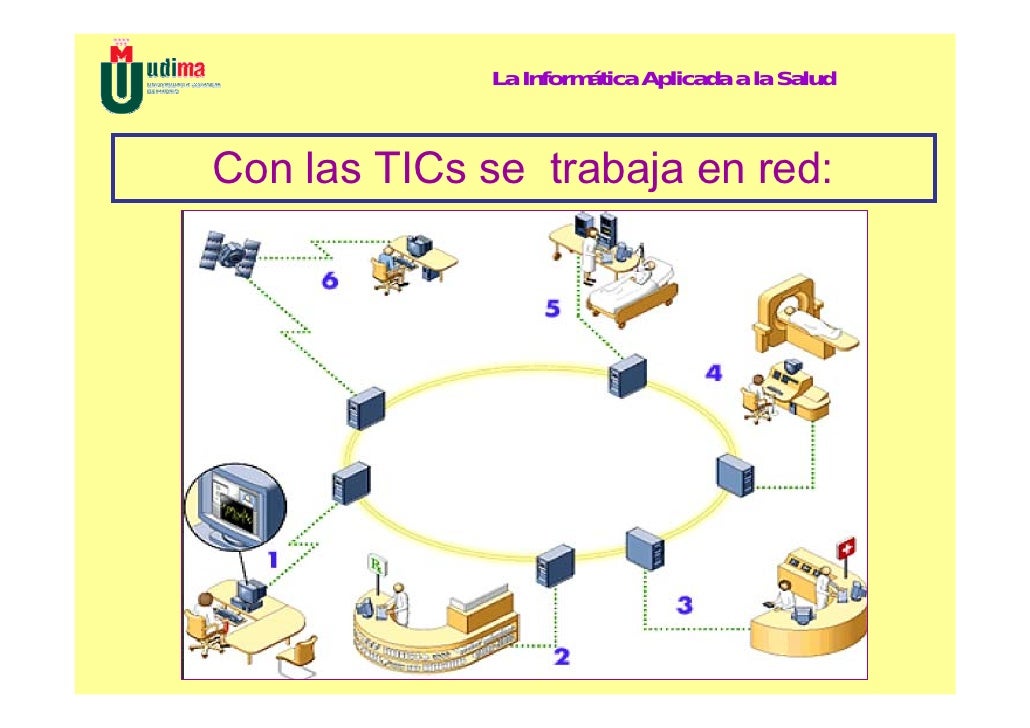

TICs en la red:

Las TICs aplicadas a la salud, presenta un desatollo muy rápido y eficiente en base a sus características:

- Trabajo en red

- Conectividad general